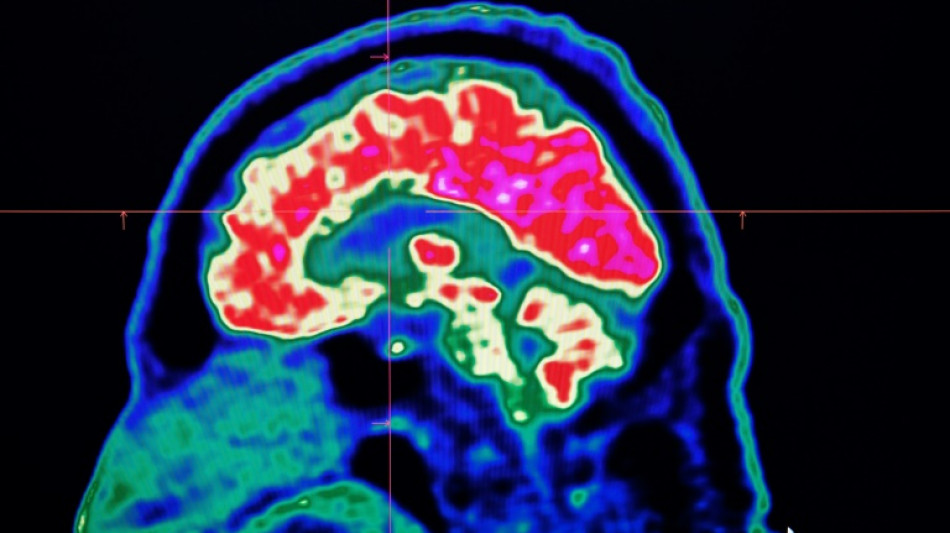

El sistema Brainomix e-Stroke, desarrollado por una empresa con sede en Oxford, permite disminuir en más de una hora el diagnóstico y escoger más rápidamente el tratamiento más adecuado.

La inteligencia artificial ayuda en la toma de decisiones a la hora de interpretar los escáneres del cerebro y así permitir que los pacientes "reciban el tratamiento adecuado, en el buen lugar y en el buen momento", destaca el ministerio.